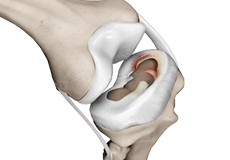

Osteochondral Defect of the Knee

An osteochondral defect, also commonly known as osteochondritis dissecans, of the knee refers to a damage or injury to the smooth articular cartilage surrounding the knee joint and the bone underneath the cartilage.